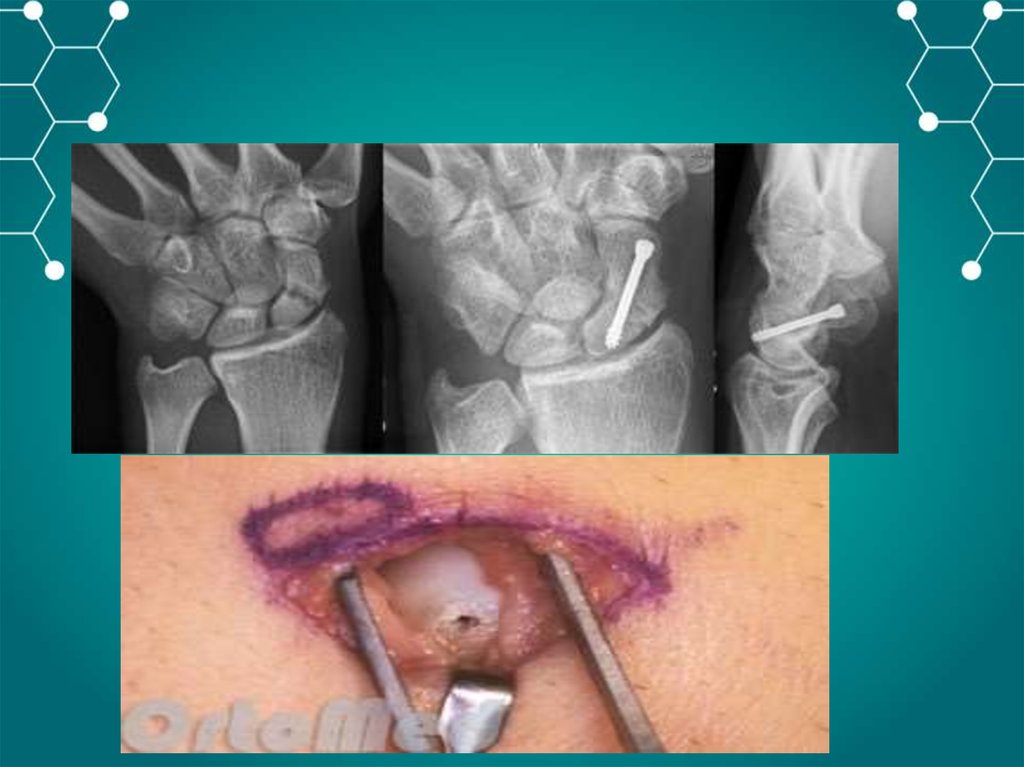

Частые перелом кисти